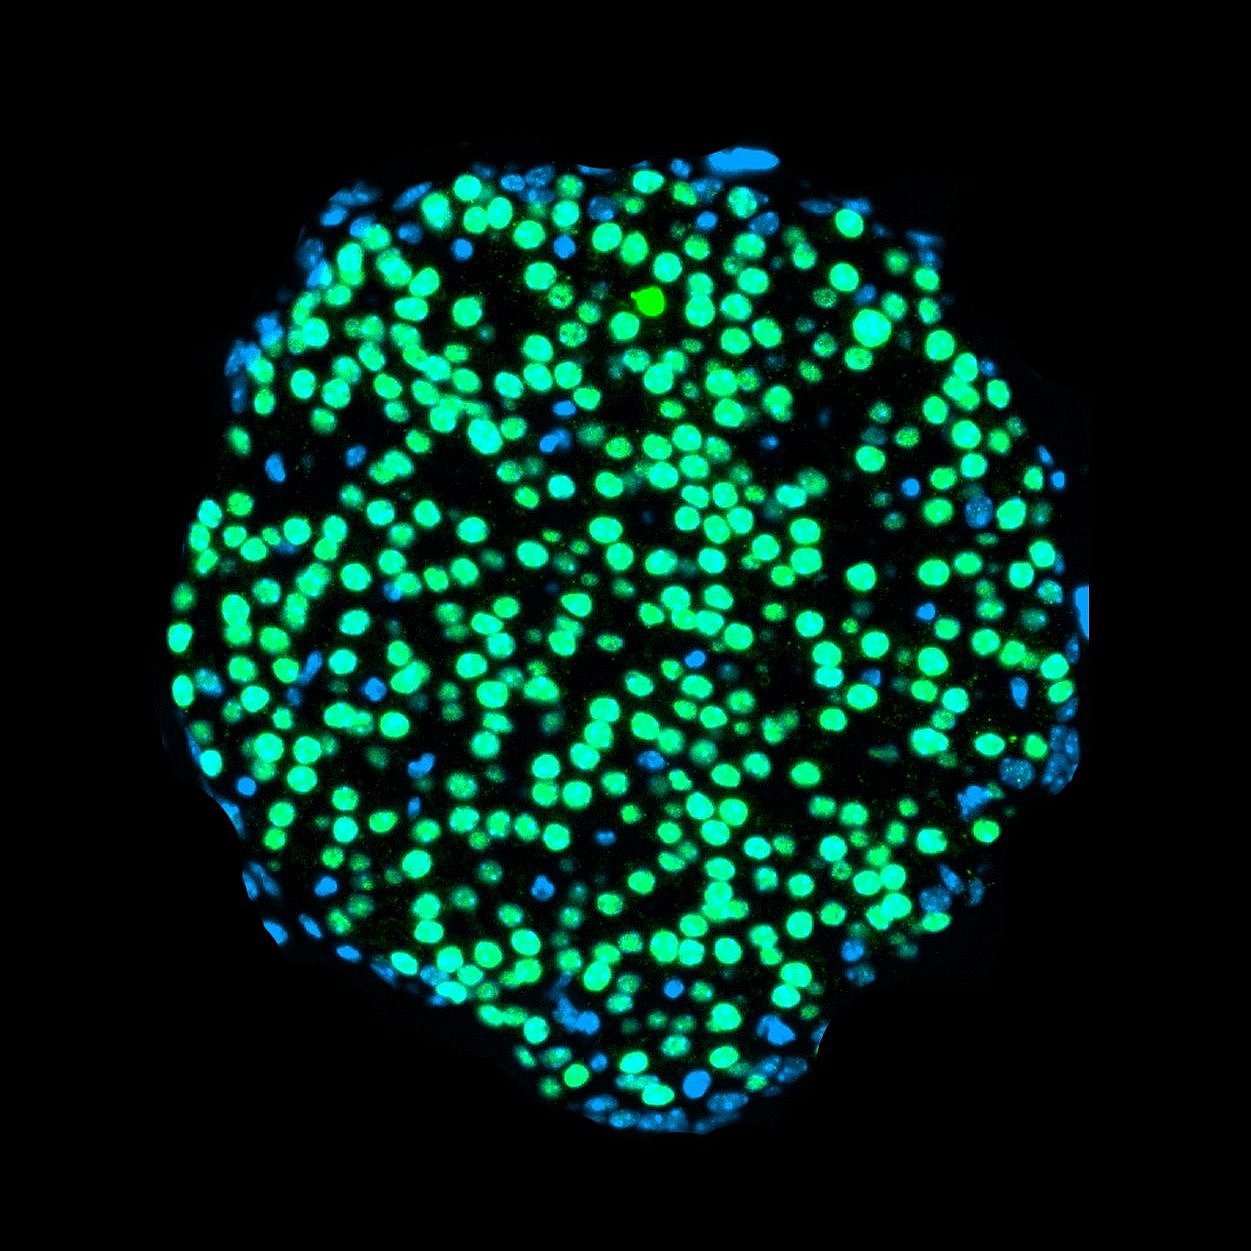

Bei den heranwachsenden Tieren hingegen arbeiteten die Beta-Zellen der Bauchspeicheldrüse nur noch eingeschränkt. Da diese für die Produktion des essenziellen Hormons Insulin verantwortlich sind, hat das schwerwiegende Folgen und führt langfristig zu Diabetes. Hierbei produziert der Körper zu wenig Insulin und der Stoffwechsel gerät aus dem Gleichgewicht. „Intervallfasten wirkt sich eigentlich positiv auf die Beta-Zellen aus. Dass in der Mausstudie junge Tiere nach dauerhaftem Intervallfasten dann weniger Insulin produzierten, hat uns deshalb überrascht“, erklärt Leonardo Matta von Helmholtz Munich, einer der Erstautoren der Arbeit.

Defekte Beta-Zellen ähneln denen von Typ-1-Diabetes-Betroffenen

Warum das passiert, konnten die Forschenden mithilfe der hochauflösenden Einzelzellsequenzierung entschlüsseln. Sie untersuchten den Bauplan der Zellen der Bauchspeicheldrüse und fanden heraus, dass sich die Beta-Zellen der jungen Tiere nicht richtig entwickelten: „Die Zellen der heranwachsenden Mäuse hörten an einem bestimmten Punkt auf zu reifen und produzierten dann weniger Insulin“, sagt Peter Weber von Helmholtz Munich, ebenfalls Erstautor der Studie. Die älteren Tiere, deren Zellen schon vor Beginn des Intervallfastens ausgereift waren, waren davon nicht betroffen.